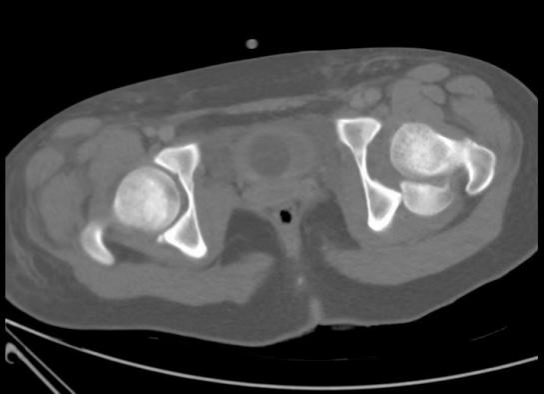

与此同时,小儿骨科·创伤骨科潘建宏主任第一时间带领团队对小张的病情进行了全面检查与评估,经诊断,明确了小张的骨折属于右侧股骨上段粉碎骨折,左侧股骨颈骺分离、Delbet分型Ⅰa型、Salter_ HarrisⅠ型骨骺损伤,骨折的股骨头骺端脱位于髋臼后侧。而这种骨折约占儿童所有骨折的万分之五,非常少见,并且手术难度大、风险大、预后差。

面对如此复杂且严重的伤情,潘主任立即组织全科进行讨论,在深入研究和综合分析,科室团队一致认为,经过股骨头骺端脱位出髋臼后侧,闭合复位不可行,应用外科脱位技术(SHD),既能最大程度保护骨折处血运、又能直视下复位,可吸收螺钉顺行固定后空心加压螺钉逆行加压固定,右侧股骨上段粉碎骨折应用青少年髓内钉固定。于是根据小张的具体情况,科室团队精心制定了一套科学、详尽的治疗方案。